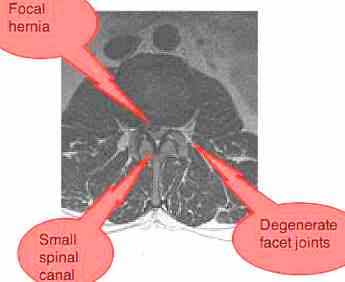

MRI (10 June)- taken after the 4th manipulation.

L1-L2: annular tear with a bulge of the disc, with narrowing of the intervertebral foramen. No nerve root compromise.

L2-L3: Focal herniation of the disc with compromise of the nerve root on the right.

L3-L4: Lumbar Stensosis: annular tear + hypertrophic facet changes + thickening of the ligamentum flavum.

L4-L5 Lumbar Stenosis, no compromise of the nerve root.

L5-S1: Moderate facet hypertrophy. No other abnormalities.

Lumbar stenosis, unlikely at his age, but with a typical trefoil shaped canal is certainly a possibility. The scan is an essential tool in the management of severe nerve impingement cases. I recommend a second opinion from a neurologist.

A: MRI reports a hernia on the RIGHT at L2-3. And lumbar stenosis in the mid and lower lumbar spine. Copy of the MRI requested.

Neurologist is guardedly positive about chiropractic. Diagnosis given: Lumbar stenosis.

The spinal stenosis at numerous levels explains the weakness in the quadriceps muscle and the great toe dorsi flexor, but most of his symptoms, and the clinical findings relate to the L5 to S1 joint where the MRI findings are least. However, the scan was taken after 4 manipulations which may have changed the findings.